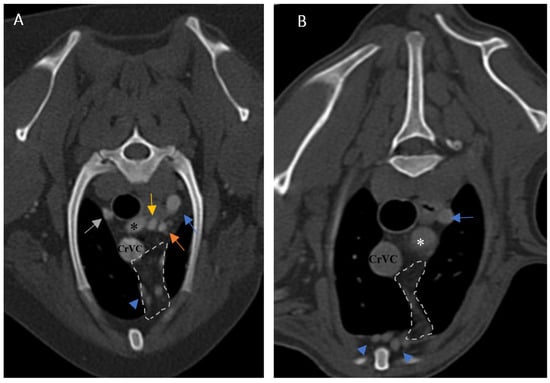

Figure 5. Demonstration of visibility and topographic location of grade 2 thymus in contrast-enhanced transverse sections of the thoracic region at the level of T3 in both patients. (A): One-year-old female mixed-breed dog with a visible, grade 2, wedge-shaped thymus with midline predominancy, mottled appearance and concave border (CT number: 75). (B): Two-year-old female mixed-breed dog with a visible, grade 2, wedge-shaped thymus with left-sided predominancy, mottled appearance and concave border (CT number: 79). Light grey dash lines illustrate thymic borders. CrVC: cranial vena cava, E: esophagus (which is dilated due to general anesthesia), blue arrow: left subclavian artery, green arrow: brachiocephalic trunk, blue arrowheads: internal thoracic arteries, yellow arrow: right common carotid artery, orange arrow: left common carotid artery, and asterisk: right subclavian artery.